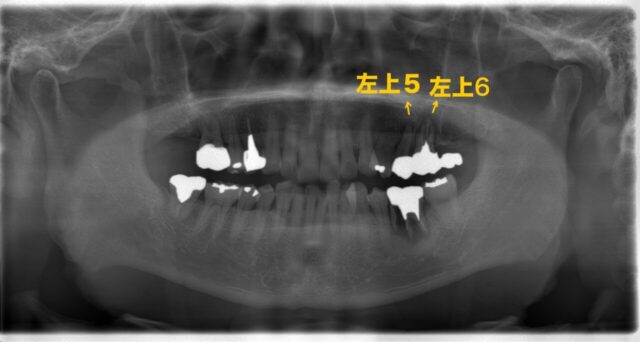

まずはレントゲン写真と口腔内写真をご覧下さい。

この写真を見て何か違和感を感じませんか?

よく見ると、奥歯にばかり治療歴があります。